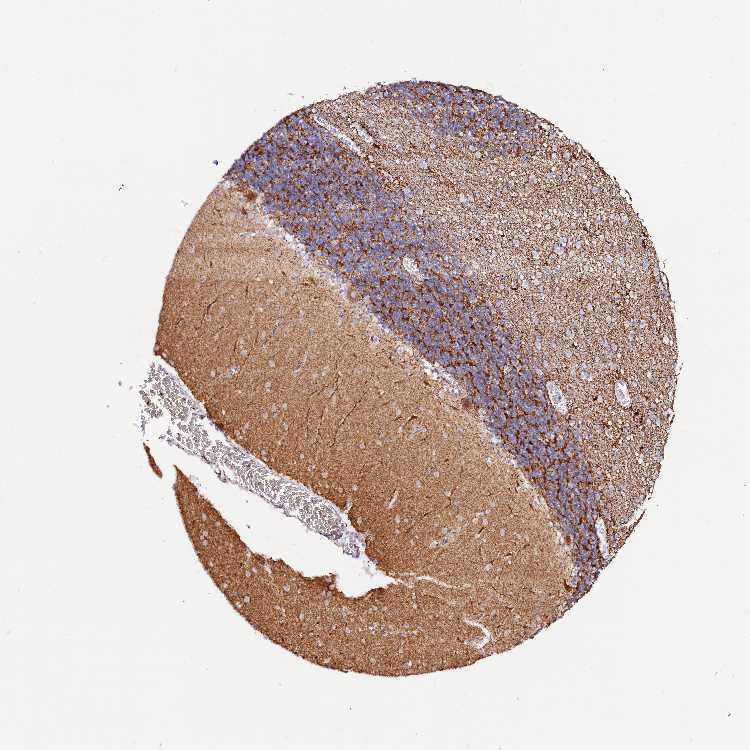

CEREBELLUM - Antibody stainingi

Antibody staining in the annotated cell types in the current human tissue is reported as not detected, low, medium, or high, based on conventional immunohistochemistry profiling in selected tissues. This score is based on the combination of the staining intensity and fraction of stained cells.

Each image is clickable and will lead to virtual microscopy that enables deeper exploration of all samples and also displays staining intensity scores, fraction scores and subcellular localization as well as patient and tissue information for each sample.

Antibody HPA002328Antibody CAB037200

Purkinje cells - cytoplasm/membrane HighHigh

Purkinje cells - dendrites Not detectedHigh

Molecular layer - neuropil MediumMedium

Processes in granular layer HighNot detected

Processes in white matter MediumHigh

Synaptic glomeruli - core HighHigh

White matter cells - cytoplasm/membrane HighNot detected